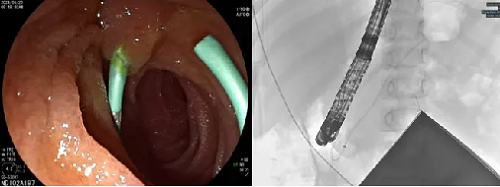

鉴于患者年龄小,对放射性敏感性高,术前医疗团队对患儿实施了严密的防护措施,并尽量缩短手术时间以减少射线对患儿的伤害。术中黄永辉使用十二指肠镜,顺利进入十二指肠降部并定位胰管开口。胰管插管比胆管插管技术要求更高,内镜下可见患儿肠腔较成人明显狭窄,操作空间十分有限,插管面临着极大的挑战。黄永辉凭借丰富经验,使用切开刀带导丝顺利插入胰管并完成胰管插管,然后沿导丝精准置入5Fr*9cm胰管支架。造影显示支架位置良好、引流通畅,手术顺利结束。

图为胰管支架置入